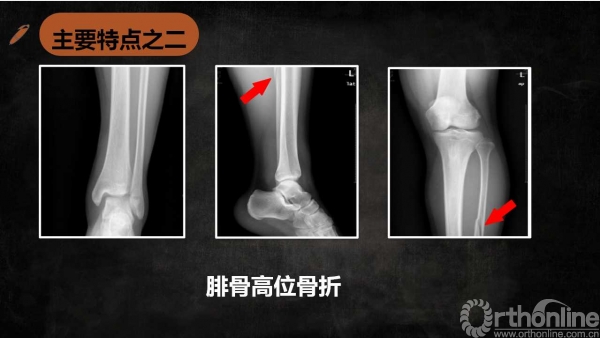

导语:特殊类型踝关节骨折虽然临床少见,但是其诊断、治疗不准确会带来诸多不良后遗症,以致踝关节功能障碍,为了让大家更好的认识特殊类型的踝关节骨折,来自湖南师范大学附属岳阳医院(岳阳市二人民医院)的伍勇医生为我们带来系列文章,第一篇为Maisonneuve骨折诊断与治疗的介绍,请详见下文分解。